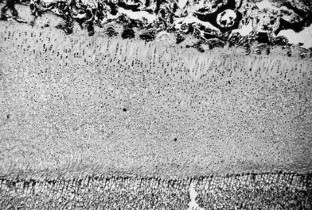

Fig. 1